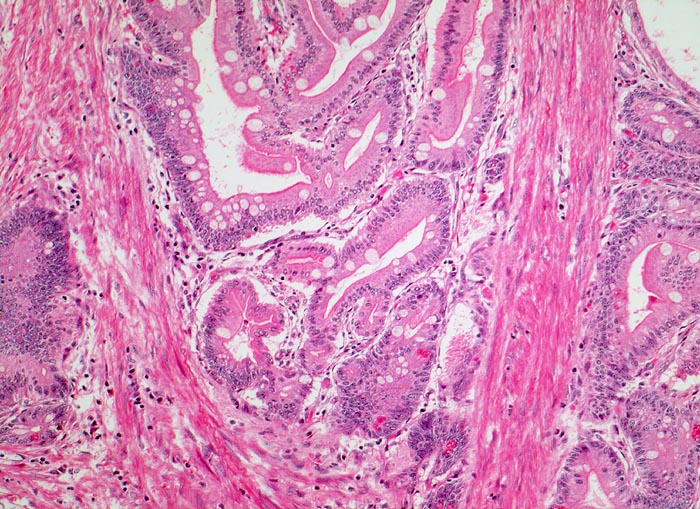

Peutz Jegher Polyp

Jejunum

Zwischen den enterisch differenzierten Epithelverbänden mit Lamina propria verlaufen breite Stränge glatter Muskulatur.

Breitbasiger Polyp von 3cm Durchmesser.

Eisenmangelanämie und wiederholte Abdominalschmerzen infolge von Intussusception.

Epithelverlagerungen in die Submukosa und Muscularis propria kommen nur in Dünndarmpolypen vor.

100